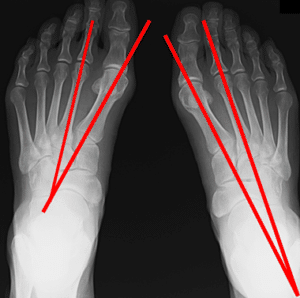

ひざ 【春日部のやぎはし整体院】ひざの整体 母趾を整える 外反母趾がひざの痛みの原因になる《春日部のやぎはし整体院が解説》 外反母趾の病因 様々な形状や性質、種類の靴が作られ、それを履くことや最近の生活様式によって、急速に増加してきています。 その要因として、以下が密接に関わりあって発生します。 外反母趾になる要因 土踏まず(内側縦アーチ)の低下=扁平足 横アーチの低下 中足...